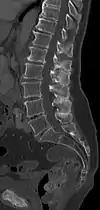

| A diagram of a human vertebral body. With Baastrup's sign, the posterior spinous process, pointing down and to the left, is abnormally thickened due to repetitive microtrauma. | |

The salient feature of the disorder is the exuberant osteophytosis that occurs at posterior lumbar spinous processes. Osteophytes are coarse calcifications at the edges of bone that form due to repetitive stress and trauma. There is also atrophy and fatty replacement of paraspinal musculature, which can be detected by CT or MRI.[5]